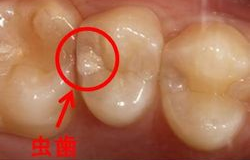

例えば、下の図のような虫歯、一見わかりにくいのですが、よく見ると白く透けて見えます。

驚くことに、中はすかすかだったのです。大きい穴の場合はプラスチックの詰め物(レジン充填)は適応しないので、保険治療であれば銀の詰め物(銀歯)にしないといけませんでした。

ハイブリッドレジンで埋められた穴

しかし、ハイブリッドレジンであれば、強度がありますので治療可能となりました。